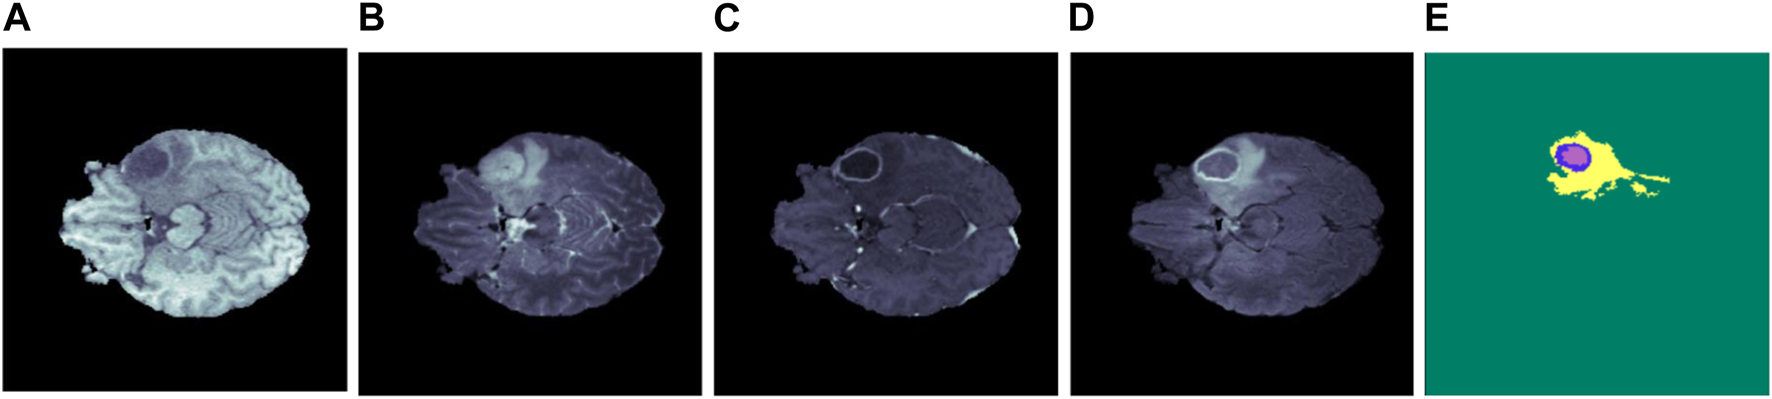

The broad use of multi-modal MRI images in the segmentation of brain tumors has been facilitated by advancements in MRI technology. This method provides a detailed interpretation of the tumors and the neighboring tissues. MRI includes four unique modalities: T1-weighted (T1), T2-weighted (T2), T1-weighted with contrast enhancement (T1ce), and fluid attenuation inversion recovery (FLAIR). These modalities provide extra information for diagnosing and monitoring brain tumors (Menze et al., 2014). Table 1 provides a detailed overview of these modalities along with their properties, and Figure 1 shows the MRI modalities of brain tumors. The T1 is frequently utilized to generate high-resolution brain images. On the other hand, T2 is useful for evaluating the fluid content in tissues, which serves as a key differentiator between tumors and healthy brain tissue. Additionally, the T1ce provides relevant details on the vascular structures and the enhancing characteristics of tumors, hence facilitating the classification of tumor types (Wang et al., 2023a).

FIGURE 1

Illustration of several brain MRI modalities (A) T1, (B) T2, (C) T1ce, (D) FLAIR, and (E) ground truth. The yellow, blue, and purple colors in the ground truth represent edema, enhancing, and necrosis, respectively.